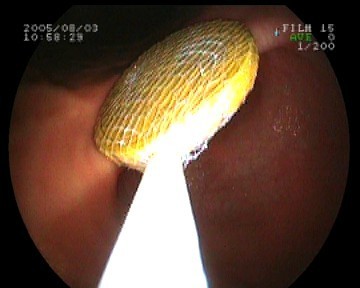

Gastroskopie - verschluckte 20-Cent-Münze im Magen - Bergung mit einer Netzschlinge